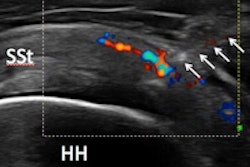

Acute case of supraspinatus tendinitis. SMI shows abnormal microvasculature (arrows) within the inflamed tendon. Image courtesy of Dr. Adrian Lim.In more than half the cases where flow was identified using both techniques, SMI was judged to be either moderately or markedly better than power Doppler. This difference was also statistically significant (p = 0.02).